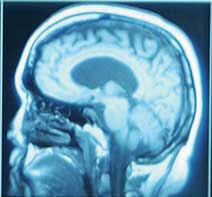

L'organisme humain possède certains gènes qui régulent l'activité antioxydante. Un de ces gènes, héméoxygénase-1 (HO-1), est supposé défendre les cellules du cerveau exposées aux attaques radicalaires. Dans de précédentes études, la curcumine, dans des cellules de rat, encourageait fortement l'expression et l'activité de HO-1, indiquant que ce composé du safran pouvait aider à enrayer les effets de l'oxydation.

Dans le but de confirmer ces données et de déterminer si la curcumine pouvait avoir des effets similaires sur des cellules du cerveau, des chercheurs ont examiné les effets neuroprotecteurs de la curcumine et sa capacité à provoquer la réponse de HO-1 dans des cultures de neurones de l'hippocampe. Le traitement par la curcumine a eu pour résultat une augmentation de l'expression de HO-1 ainsi qu'une expression plus importante des enzymes antioxydantes. La pré-incubation des cellules dans la curcumine augmentait la résistance des cellules aux lésions oxydatives.

Selon les chercheurs, cette étude indique que la curcumine pourrait être utilisée dans un but thérapeutique comme un puissant inducteur de HO-1 qui pourrait protéger les cellules du cerveau contre les lésions oxydatives. Les chercheurs réclament des études supplémentaires in vitro et in vivo pour déterminer si la curcumine peut prévenir les maladies neurodégénératives.